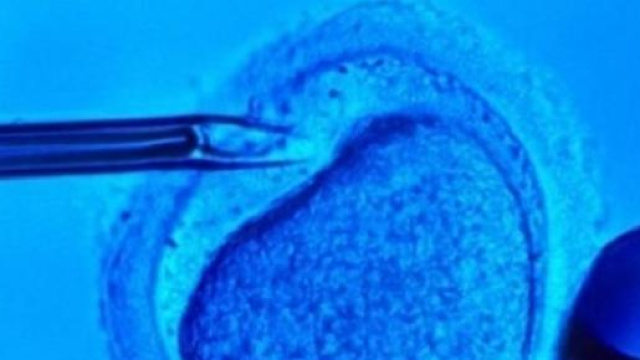

Per la prima volta nella storia della scienza, embrioni umani sono stati modificati geneticamente. L'esperimento è stato portato a termine da un gruppo di ricercatori cinesi dell'Università Sun Yat-sen di Guangzhou.

La ricerca dell'equipe cinese, guidata dal professore di biologia Huang Junjiu, aveva l'obiettivo di correggere la mutazione di un gene che provoca la beta-talassemia, una malattia diffusa in Cina, attraverso la modifica di embrioni umani.

L'esperimento si è avvalso di una tecnica di recente scoperta, la CRISPR/Cas9, che permette di riconoscere il gene difettoso e correggerlo in embrioni al primo stadio che andranno a sviluppare un organismo composto da cellule tutte modificate, in grado di trasmettere la modifica alle generazioni future.

Secondo i dati pubblicati, la ricerca si è svolta su 86 embrioni umani, non utilizzabili per la generazione, ma solo in 28 casi si è verificata la mutazione genetica desiderata. Un dato insufficiente per poter considerare un successo l'esperimento cinese e che, oltre a sollevare dubbi di carattere etico sull'opportunità di modificare geneticamente embrioni di esseri umani, genera interrogativi inquietanti proprio per la incertezza dei risultati e l'incontrollabilità di eventuali effetti non desiderati.